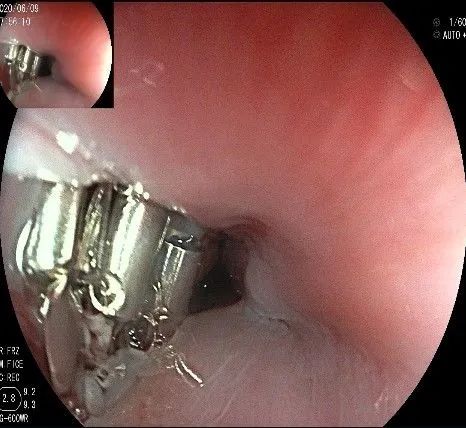

瘤子切除后,在粘膜切开的地方,固有肌层的纵形肌处形成一个开口。

倒镜观察,隆起已经消失。

夹闭创面的时候做胃镜吸引,利于创面闭合。

创面夹闭完成,反复冲洗观察,无出血及穿孔。结束手术,等待病理结果。